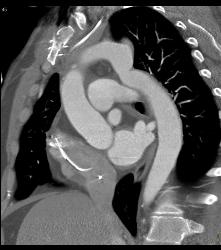

Prior Repair of Coarctation of the Aorta